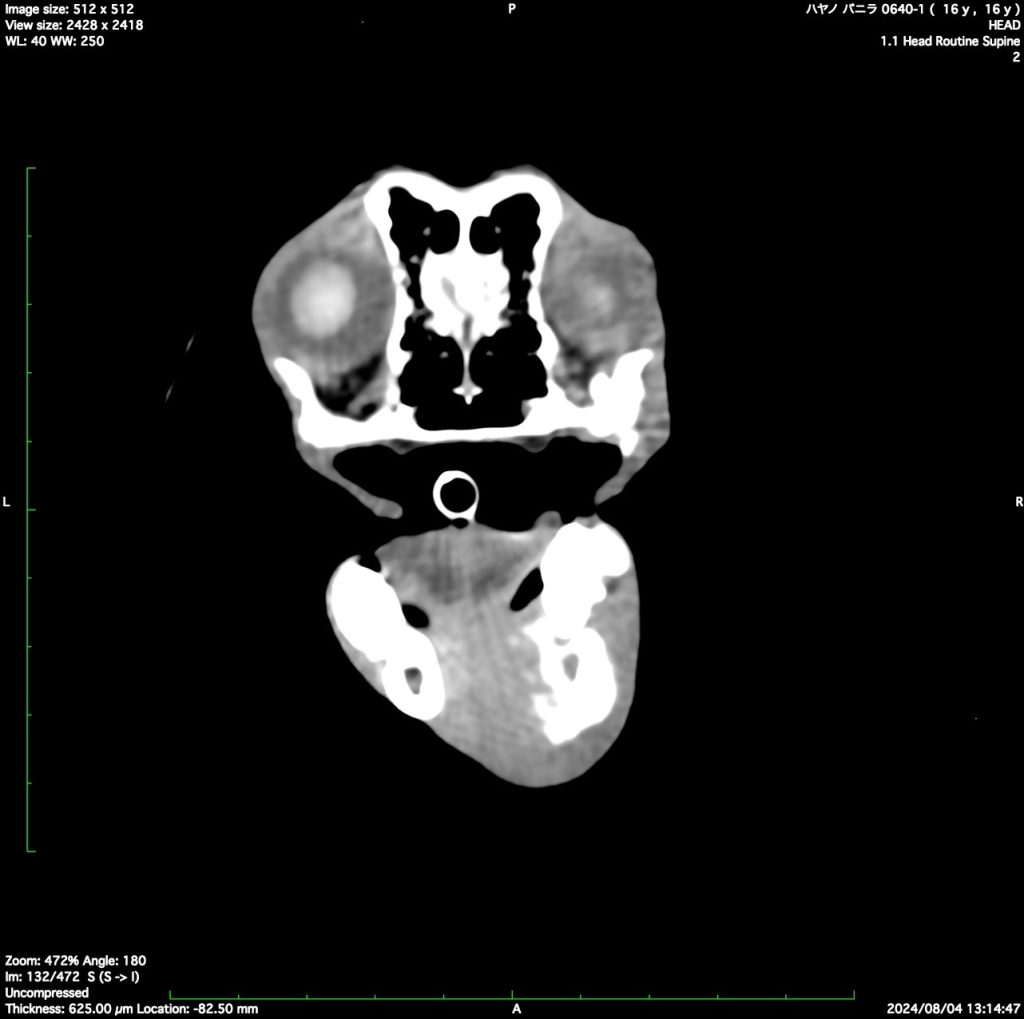

- 口腔がん(扁平上皮癌、メラノーマ(悪性黒色腫)、繊維肉腫など)

- 鼻腔内のがん(軟骨肉腫、扁平上皮癌、リンパ腫など)

鼻腔の腫瘍

扁平上皮癌

鼻腔内リンパ腫

軟骨肉腫